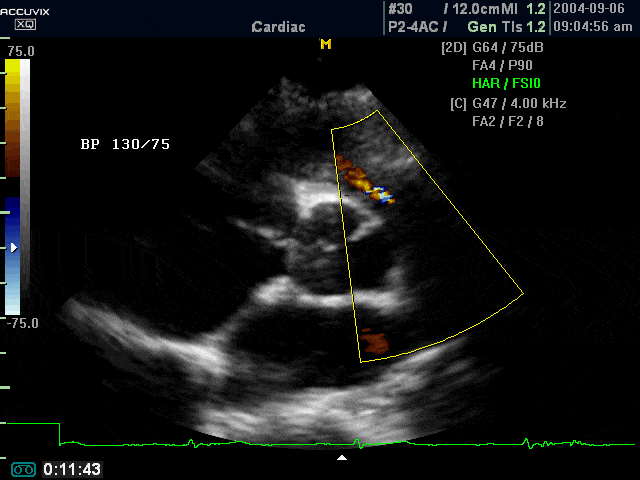

Pulmanic artery, color doppler (echogramm №367)

[RU] Ultrasound image №367: Heart (pulmanic artery) in color doppler mode.

Echogramm was received by ultrasound scanner Accuvix-XQ (out of production).